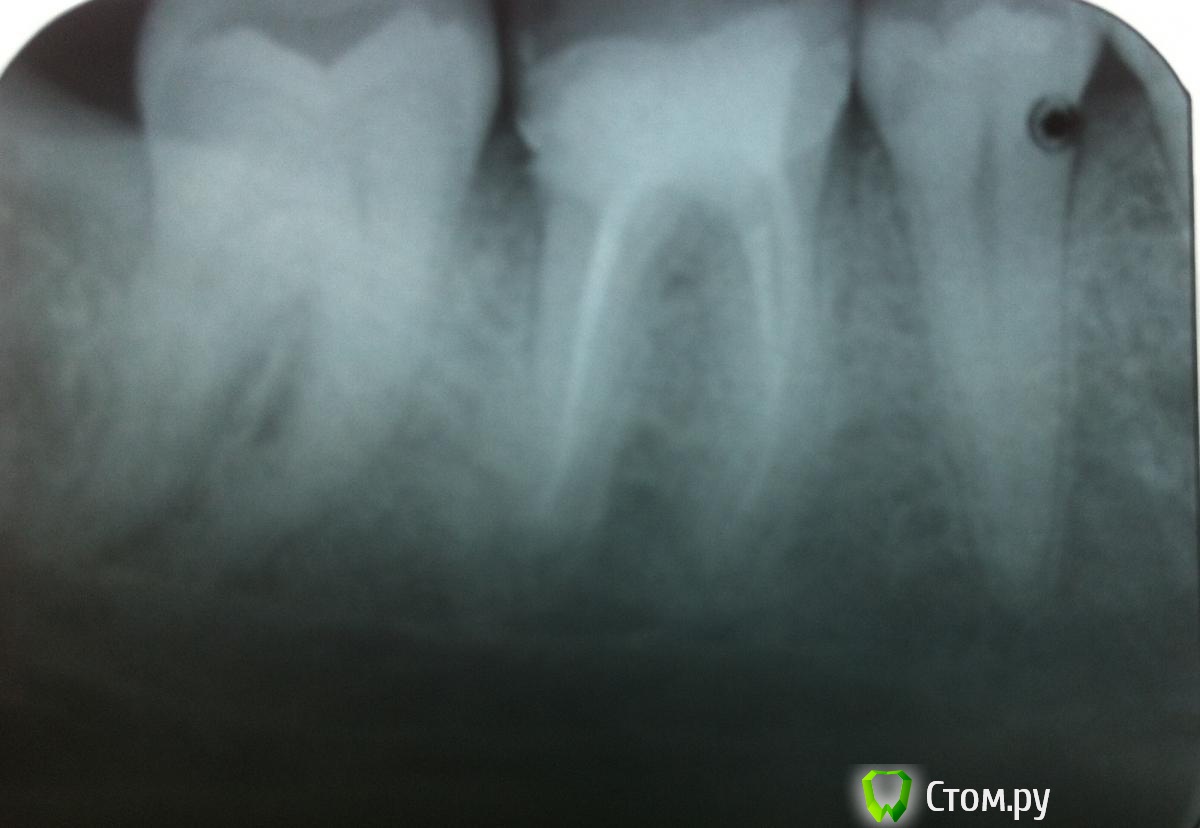

Aalsol Опубликовано 4 июня, 2014 Автор Поделиться Опубликовано 4 июня, 2014 (изменено) А трещина которая в корень уходит влияет как то на решение?И не могли бы вы описать в кратце алгоритм лечения? чтобы понимать о чем говорить и что предлогать доктору?вот еще попробывал переснять снимок Изменено 4 июня, 2014 пользователем Aalsol Ссылка на комментарий

DokDent Опубликовано 4 июня, 2014 Поделиться Опубликовано 4 июня, 2014 А трещина которая в корень уходит влияет как то на решение?И не могли бы вы описать в кратце алгоритм лечения? чтобы понимать о чем говорить и что предлогать доктору?вот еще попробывал переснять снимокDSCN0630.JPG Влияет. Вот чтоб было понятно-наглядный пример: (фото из журнала "Медицинский совет) Вообще-то доктор должен предлагать Вам план лечения, а не Вы ему Ссылка на комментарий

red_butler Опубликовано 5 июня, 2014 Поделиться Опубликовано 5 июня, 2014 Спасибо! Но всетаки если лечение, то что оно должно предусматривать? Каков план?И почему тогда доктор настаивает на удалении? Не предлагая полечить?нам приходится отвечать, опираясь только на снимок не совсем хорошего качества. Нужен очный осмотр, возможно план будет понятен только после удаления пломбы и/или компьютерной томограммы. Сходите еще на консультацию к другим врачам Ссылка на комментарий